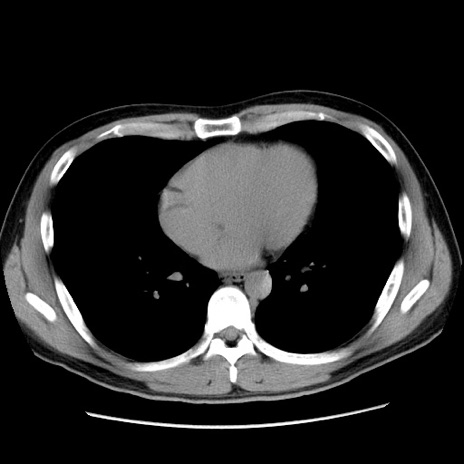

症例36(横断像)

【症例】20歳代 男性

【主訴】心窩部痛

【現病歴】今朝より上腹部痛あり。一旦軽快していたが再度出現したため救急要請。昨日夕に白身の魚を含む刺身を食べた。

【身体所見】BP 136/89mmHg、HR 74/min、BT 37.0℃、腹部:膨満、軟、心窩部に圧痛あり。反跳痛なし、筋性防御なし、腸雑音やや亢進あり。

【データ】WBC 17700、CRP 0.48